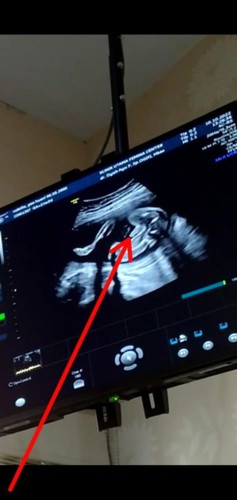

Mau cerita bunda, kemaren abis USG diusia 21w 2 hari dimarahin ibu dokter gara gara selama kehamilan BB aku naik drastis, BB awal 60 sekarang 73. dikira aku mah kalo hamil bebas makan apa aja, ketambah selama hamil aku engga ngerasain mual muntah malah doyan makan, ada yang sama engga disini hamil disuruh diet😅?#ingintahu #seriusnanya